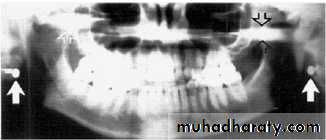

Stud earrings, real shadows (solid arrows)

with ghost shadows (open arrows).Tongue bar projected over palate

Lead apron artifact

A necklace